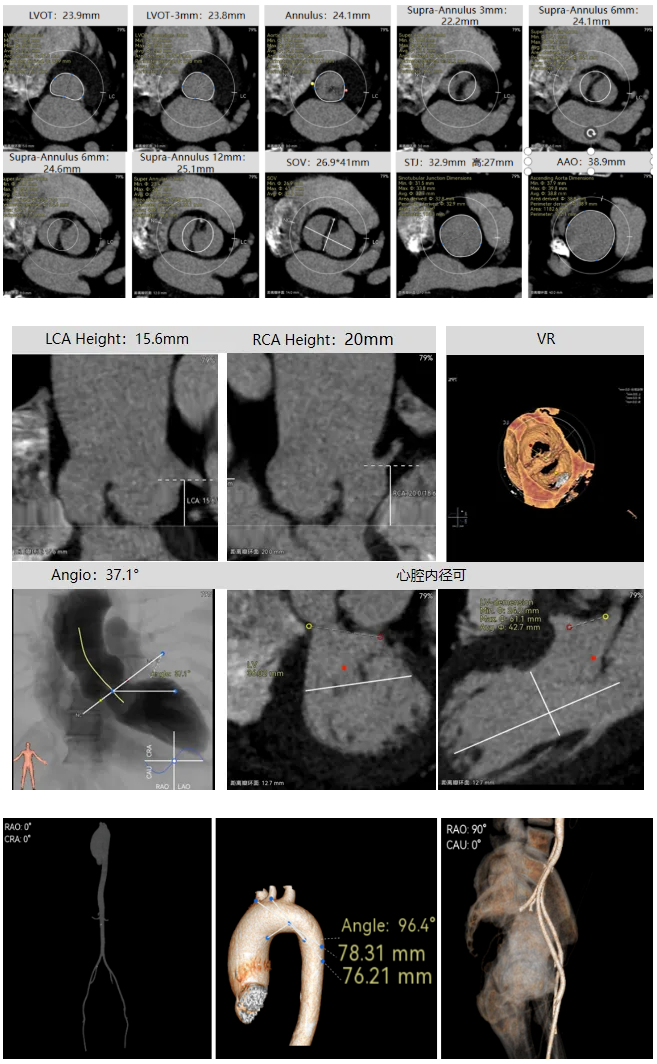

袁祖贻院长 西安交通大学第一附属医院 创新见证中国领跑,数据积累筑牢临床效果 韩克教授 西安交通大学第一附属医院 干瓣技术革新赋能特殊人群治疗,“量体裁衣”筑牢安全防线 患者病史 主诉与现病史:5年前因"血友病,血尿”就诊于当地医院,住院期间行心动超声提示主动脉瓣及二叶瓣畸形,无胸闷气短,无胸痛,咳嗽咳痰,无头晕,恶心呕吐等不适。未予以干预,后规律复查心超,3周前复查心超提示:主动脉瓣二瓣化畸形并重度狭窄,升主动脉内径明显增宽。 既往史:确诊血友病A型40年 术前超声提示:先天性主动脉瓣二叶式畸形,主动脉瓣中度狭窄,升主动脉增宽,左室舒张功能减低,EF73% 术前CT:Type0型二叶瓣,瓣叶增厚无钙化,主动脉瓣环径24.1mm,LVOT23.9mm;双侧冠脉开口高度可,窦部空间可,STJ、升主动脉内径可;预估冠脉低风险;主动脉水平夹角37.1°,主动脉弓角、弓距可;左室内径可;外周入路无明显迂曲,无钙化;双侧股动脉内径可,右侧股动脉低分叉。 手术策略 推荐右侧股动脉为主入路,左侧股动脉为辅入路。右股分叉上方1mm穿刺;仅舒张期时相,需根据球扩结果评估瓣膜尺寸,推荐使用18mm球囊进行预扩;预装AV26瓣膜。 手术过程 在右股动脉穿刺建立通路后,顺利送入大鞘。18mm球囊预扩后评估无腰无漏,后将Prostyle A® AV26瓣膜精准释放于目标位置,术后即刻造影显示无明显反流,无瓣周漏,平均跨瓣压差由术前的100mmHg降至2mmHg,患者血流动力学显著改善,术后超声证实瓣膜启闭良好。 主动脉根部造影 18球囊预扩 定位 稳定释放后脱钩 最终造影形态位置良好 外周血管造影,无血管并发症 术后超声显示无生物瓣位置固定瓣膜功能正常,无瓣周漏。 Prostyle A®预装干瓣——助力临床最优化解决方案 流入端桶状设计:流入端桶状的设计,锚定迅速,有效减少释放步骤,提升植入稳定性; 平衡的收腰设计:二叶瓣患者对瓣膜径向支撑力提出更高要求,Prostyle A®均衡的收腰设计可更好适应二叶瓣解剖,保证了EOA,有效降低了循环崩溃风险,提高瓣膜的耐久性; 预装干瓣 便捷顺安:金仕生物专利抗钙化技术运用纳米技术去除组织内的细胞碎片和磷脂,封闭游离醛基,从根本上阻断了瓣膜钙化的多项因素,显著提升了瓣膜的耐久性;同时,相比较传统戊二醛保存方式,干式存储最大限度的保留心包的亲水亲油平衡,还原组织天然曲柔性,进一步保障了瓣叶开合,保证长期耐久性。 专家简介 袁祖贻 西安交通大学第一附属医院(点击查看专家详细简历) 韩克 西安交通大学第一附属医院(点击查看专家详细简历) · END ·